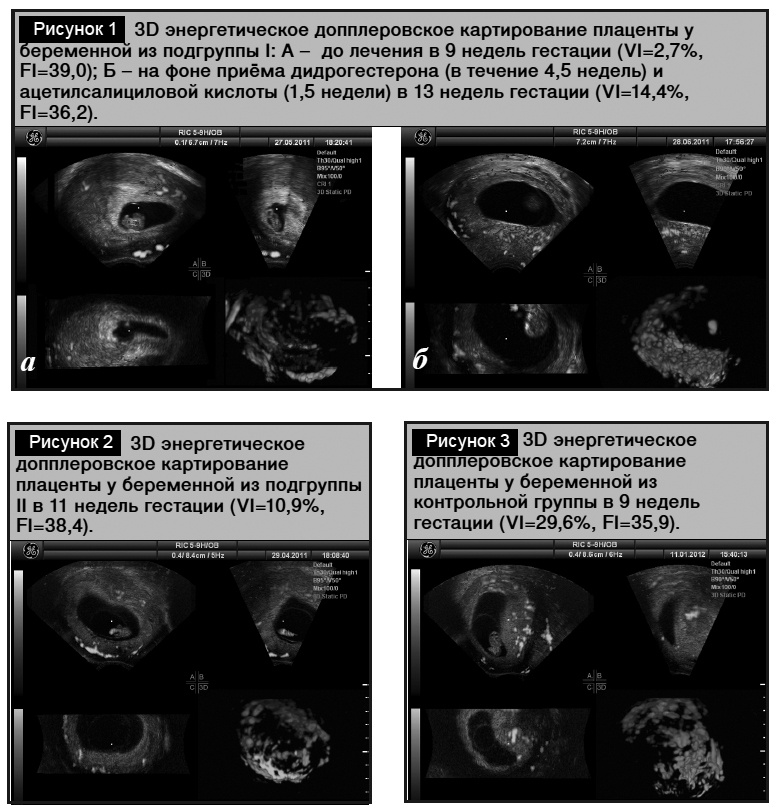

Исследования плацентарного кровотока методом 3D-допплерометрии в подгруппе I до начала приема дидрогес-терона и ацетилсалициловой кислоты, и изначально в подгруппе II выявили низкие значения VI плаценты в отличие от таковых в группе контроля (р=0,006) (табл. 3). Скорость роста VI плаценты с 8-й по 15-ю неделю гестации в подгруппе I после начала терапии дидрогестероном и ацетилсалициловой кислотой была в 1,6 раза выше, чем в подгруппе II (р=0,07) (рис. 1а, 1б, 2). На фоне терапии дидрогестероном с 8-й по 15-ю неделю с включением ацетилсалициловой кислоты с 13-й недели гестации VI плаценты в подгруппе I имел тенденцию к снижению в 1,3 раза в сравнении с таковым в группе контроля (р=0,07), тогда как в подгруппе II продолжали наблюдать гиповаскуляризацию с уменьшением VI плаценты в 1,9 раза (р=0,01) в сравнении с таковым в группе контроля (рис. 3). В подгруппе I на фоне терапии дидрогестероном и ацетилсалициловой кислотой обнаружено снижение FI, соответствующее уменьшению перфузии плацентарного ложа матки в 1,4 раза (p=0,002). В подгруппе II значения FI не отличались от таковых в группе контроля (p=0,24).

Терапия дидрогестероном и ацетилсалициловой кислотой в I–II триместре гестации увеличивала плацентарную васкуляризацию, но снижала перфузию плаценты, определяя непрерывный кровоток в области плацентарного ложа, препятствующий ишемии и реперфузии. Снижение плацентарной перфузии на фоне приема дидрогестерона и ацетилсалициловой кислоты определяет низкое содержание кислорода в матке, защищает трофобласт от разрушения свободными радикалами кислорода, блокируя оксидативный стресс в плаценте [28].